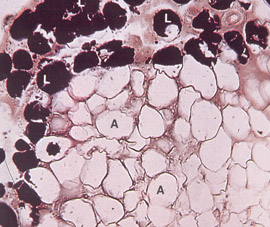

脂肪组织3